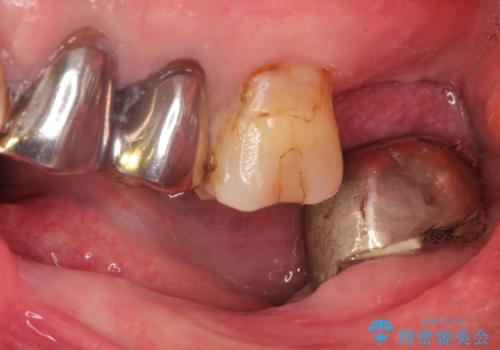

- 奥歯がなくて咬めないのと、全体的に見た目をよくしたいとのことで来院されました。

下顎の両側の奥歯が欠損しており、入れ歯をお持ちでしたが、うまく咬めずにほとんど使用していない状態でした。

上顎は全体的にクラウンの入れ替えと、下顎はインプラントの提案もしましたが、希望されなかったのでノンクラスプデンチャーの製作をする治療計画としました。

奥歯が欠損しており、上下の前歯が強く咬合する可能性があったので、上顎前歯の裏側は金属のものにしました。